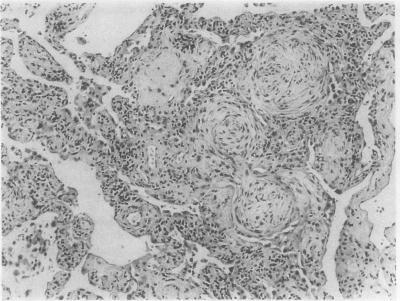

Cryptogenic organising pneumonitis (bronchiolitis obliterans organising pneumonia) is an uncommon condition that often responds to steroids. It is characterised clinically by constitutional symptoms, pathologically by intra-alveolar organising fibrosis, and radiologically by patchy pulmonary infiltrates. Its full clinical spectrum and course are only partially described and understood. Six patients are described, seen over three years, with considerably diverse clinical and radiological presentations (two had diffuse lung infiltrates, two had peripheral lung infiltrates, and two had localised lobar involvement) and with very varying severity of disease (two with a life threatening illness, three with appreciable subacute constitutional symptoms, and one with mild symptoms). It is concluded that cryptogenic organising pneumonitis can present in various ways. A set of diagnostic criteria are proposed which will help in the recognition of this syndrome, which is probably underdiagnosed.

隐源性机化性肺炎(闭塞性细支气管炎机化性肺炎)是一种不常见的疾病,通常对类固醇治疗有反应。其临床特征为全身症状,病理特征为肺泡内机化性纤维化,放射学特征为斑片状肺部浸润。其完整的临床谱和病程仅得到部分描述和了解。本文描述了6例患者,这些患者在3年期间就诊,临床表现和放射学表现差异很大(2例有弥漫性肺部浸润,2例有外周肺部浸润,2例有局限性肺叶受累),疾病严重程度也非常不同(2例患有危及生命的疾病,3例有明显的亚急性全身症状,1例有轻度症状)。得出的结论是,隐源性机化性肺炎可以有多种表现形式。提出了一套诊断标准,这将有助于识别这种可能诊断不足的综合征。